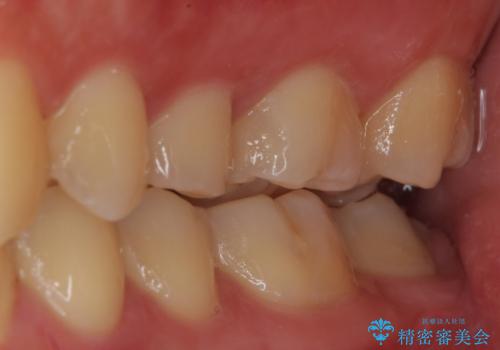

歯に穴が開いた セラミックインレー修復

- 当院でインビザラインによる矯正治療が終わった患者様です。

矯正治療終了時歯に穴が開いたとのことで、治療を希望されました。

拡大鏡視野化にて、虫歯を除去し、セラミックインレー(セラミックの詰め物)に適した形に整えました。